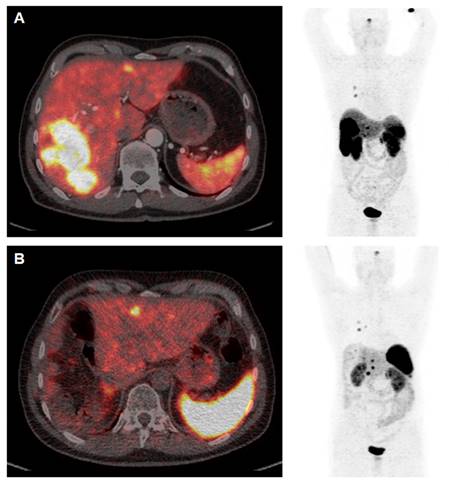

Figure 3

[68Ga]Ga-DOTATOC PET/CT Study Prior to (A) and 12 weeks after (B) Cytoreductive Surgery. The patient (64 y) was diagnosed with medullary thyroid cancer (MTC) at stage pT1a N1a R0 Mx in 2005. After complete thyroidectomy in July 2005 the disease was stable until 2014 when SSTR-positive liver metastases were diagnosed. PRRT with [177Lu]Lu-DOTATATE (accumulated activity 29.47 GBq) then resulted in disease stabilisation until January 2022. Appearance of increased size of liver metastases (A) were associated with increased episodes of watery diarrhea, not responsive to symptomatic therapy. In April 2023 the patient underwent cytoreductive surgery (B) and currently receives a postsurgery second period of [177Lu]Lu-DOTATATE PRRT. Symptoms are completely relieved and the patient has gained >10 kg body weight (September 2023).

Recently, Minczeles et al. [102] reported that early administration of PRRT followed by surgery is associated with favourable long-term outcomes in patients with locally advanced or oligometastatic pNET and can be considered for selected patients with vascular involvement and/or increased risk of recurrence. Two clinical studies are currently recruiting patients with either GEP-NET [103] or pNET [104] receiving neoadjuvant PRRT followed by surgery.

We include a clinical case of a patient with medullary thyroid cancer with mainly liver metastases who improved dramatically with the combination of cytoreductive surgery and PRRT (Figure 3).